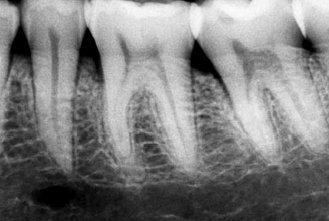

5- Lesiones periodontales como perdida ósea vertical y lesiones de furca en multirradiculares, concomitantes con alteración pulpar.

Este tipo de lesiones deben ser evaluadas como parte de un proceso de deterioro pulpo-periodontal concomitante o no.

Es sabido que lesiones periodontales afectan la biología pulpar, llevando a un proceso de necrosis pulpar. Y que lesiones pulpares del tipo necrótico producen manisfestaciones en la lámina periodontal. (lesion de furcación)

La radiografía periapical es un elemento valioso para detectar este tipo de lesiones, por su nivel de detalle ,contraste y bajo costo.